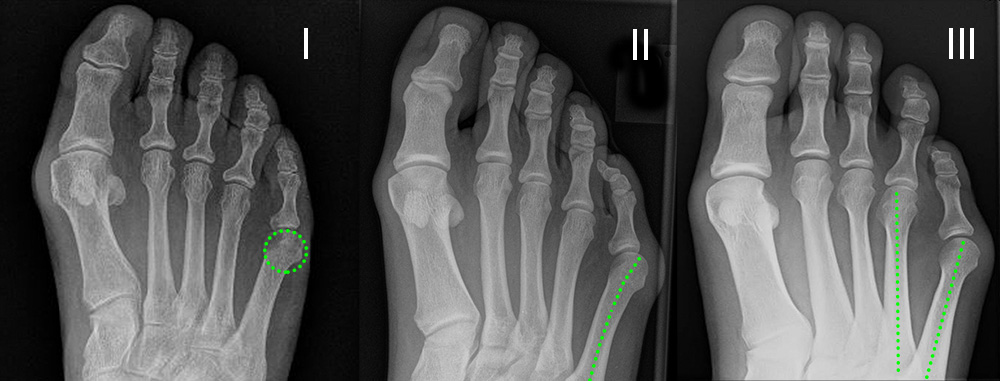

Eines der häufigsten diabetischen Ulcera befindet sich unter dem Os metatarsale I-Köpfchen (Abb. 9). In einer Kohorte von 61 Patienten mit diabetischer Neuropathie und Ulkus war diese Lokalisation mit 43 % am häufigsten (Abb. 10) 24.

Um die Steilstellung des ersten Os metatarsale und die damit verbundene Entwicklung eines plantaren Ulkus unter MTK-1 zu verhindern, kann in minimalinvasiver Technik durch eine schräg verlaufende, dorsalbasige Keilosteotomie im proximalen Anteil des Os metatarsale I das Metatarsaleköpfchen angehoben werden. Diese Maßnahme führt zu einer Druckreduktion und in der Regel zu einer Abheilung des Ulkus. Die Osteotomie wurde 1998 erstmalig in der offenen Technik beschrieben, wird aber inzwischen auch in minimalinvasiver Technik durchgeführt 25. Über einen dorsomedialen Hautschnitt wird am ersten Strahl ein dorsalbasiger, nach distal geöffneter Keil reseziert (Abb. 11). Der Eintrittspunkt der Fräse befindet sich knapp distal des Tarsometatarsale-I-Gelenks. Die plantare Kortikalis des Os metatarsale I wird dabei erhalten. Die Breite des dorsalen Keils bestimmt das Ausmaß der Korrektur und kann durch Verwendung einer entsprechenden Fräse modifiziert werden. Durch einen Keil mit einer Basis von 3,4 mm lässt sich das Os metatarsale I um ca. 5° anheben. Hat der dorsale Keil eine Basis von 6,7 mm, wird die Achse des Os metatarsale I um 10° nach dorsal korrigiert (Abb. 12). Wird eine Korrektur von ca. 5° angestrebt, bietet sich an, eine Fräse mit einem Durchmesser von 2 mm zu verwenden. Der Substanzverlust bei einem Schnitt liegt bei 2-2,5 mm. Für eine weitere Knochenresektion wird die Osteotomie durch plantaren Druck auf das Os metatarsale I Köpfchen geschlossen und die Fräse nochmals durch die geschlossene Osteotomie geführt. Durch mehrmalige Wiederholung dieser Prozedur lässt sich die Korrektur sehr genau einstellen. Für eine Korrektur von 10° oder mehr kann eine Keilfräse mit entsprechend größerem Durchmesser verwendet werden. Nach Schließen der Osteotomie erfolgt die temporäre Fixation mittels eines K-Drahtes und die Osteosynthese mit einer oder zwei Zugschrauben. Die Nachbehandlung beinhaltet eine sechswöchige Ruhigstellung im Verbandsschuh unter Fersenbelastung.